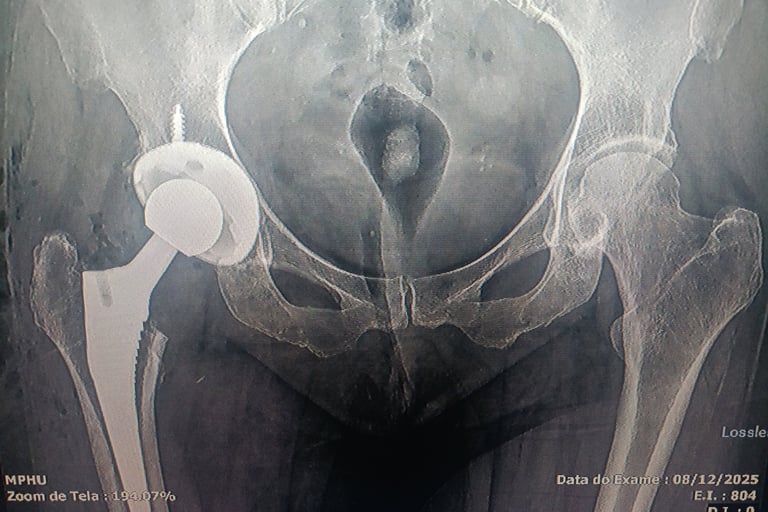

- Tratamento cirúrgico de fraturas ( transtrocanteriana, subtrocanteriana, diafisária de fêmur, acetábulo )

- Cirurgias de quadril ( prótese de quadril, síndrome do impacto, osteonecrose da cabeça do fêmur, síndrome do piriforme )